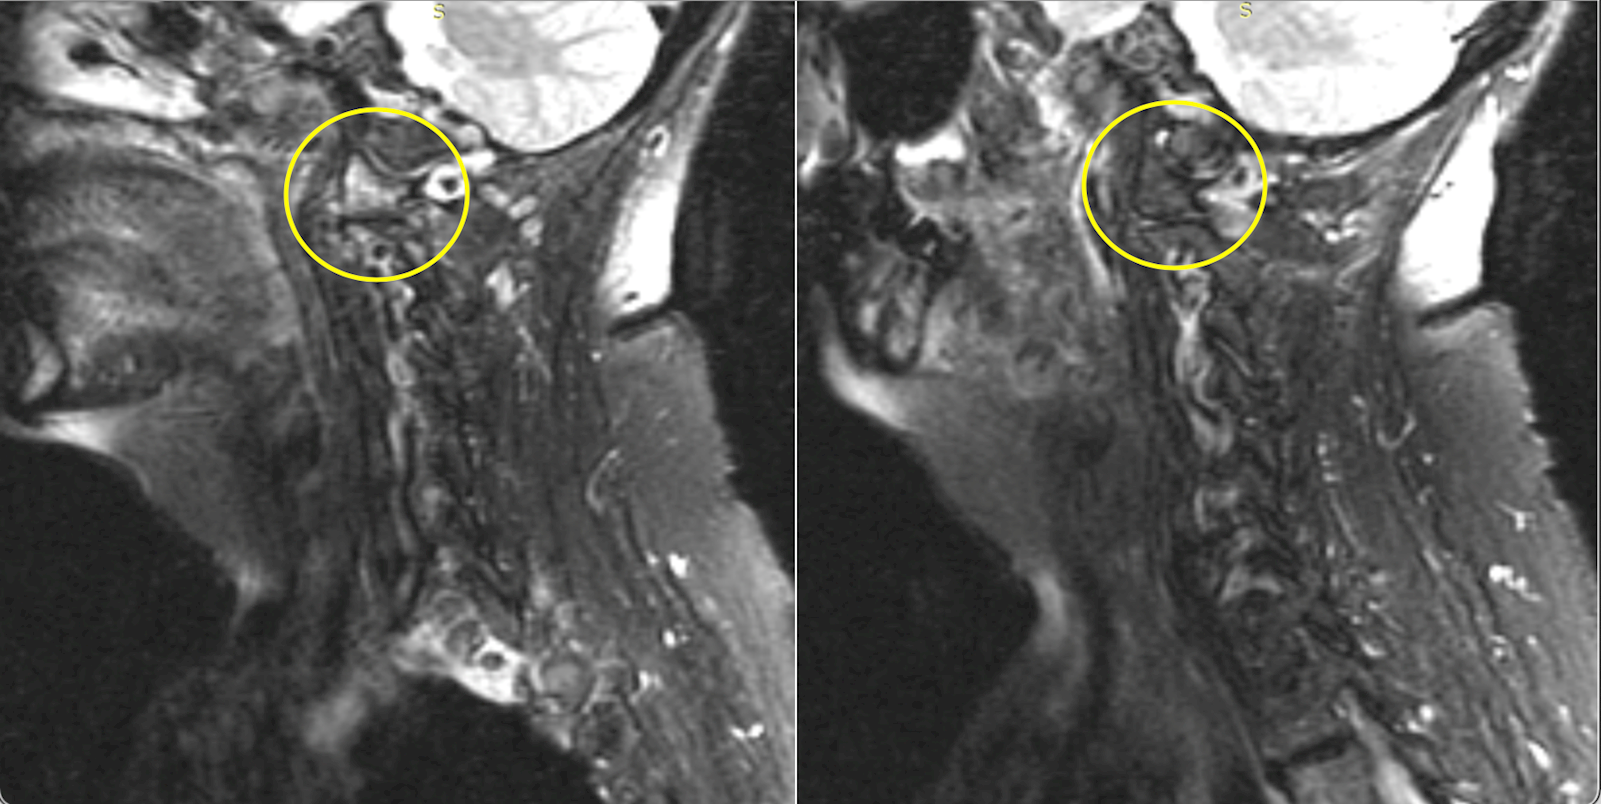

The PCP ordered an MRI with and without contrast. A radiologist reported bone marrow edema as evidenced by increased signal intensity on T2WI and decreased signal intensity on T1WI of the right C1 lateral mass and C2 vertebra. This was consistent with acute occult fracture (Images 2 and 3). While CT could confirm the diagnosis, it was not ordered or performed by the PCP, despite the recommendation.

xrays